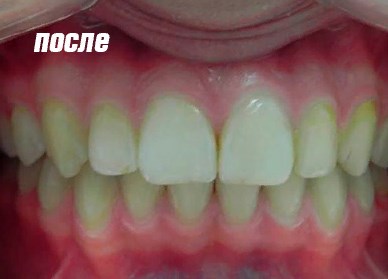

Результат восстановления зубов